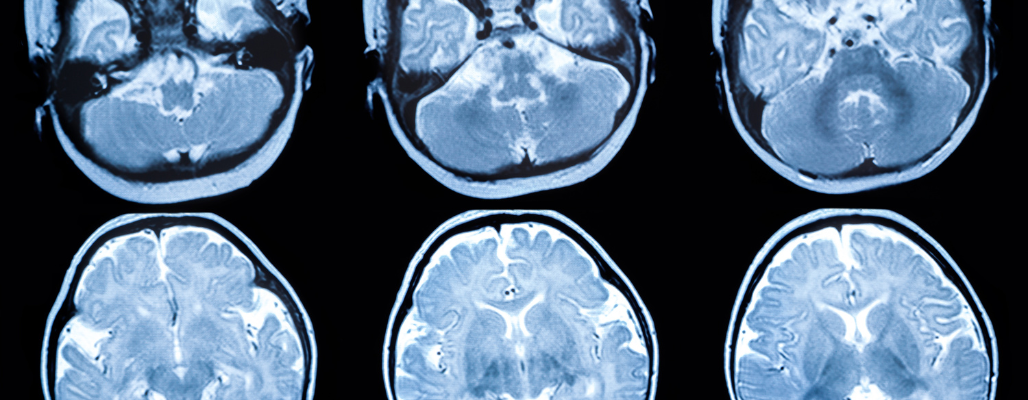

• Resonancia magnética (RM): muestra patrones característicos de pérdida de sustancia blanca.